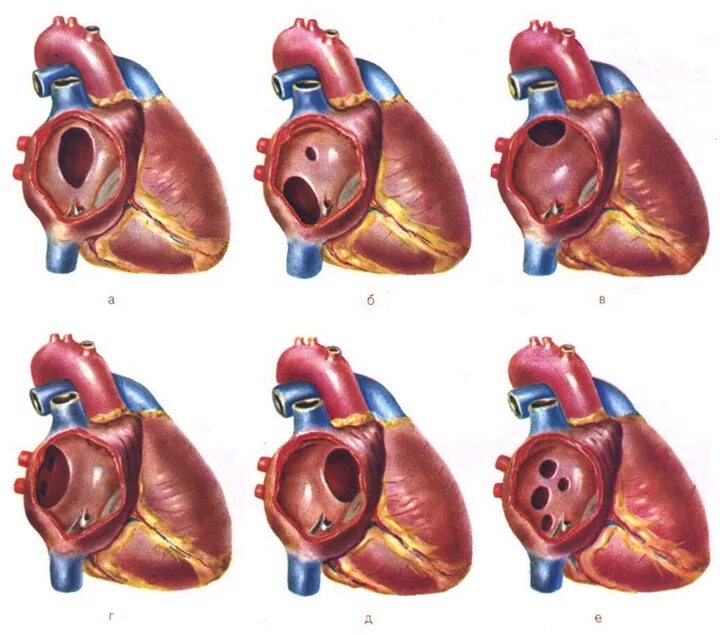

Окно в сердце у новорожденного